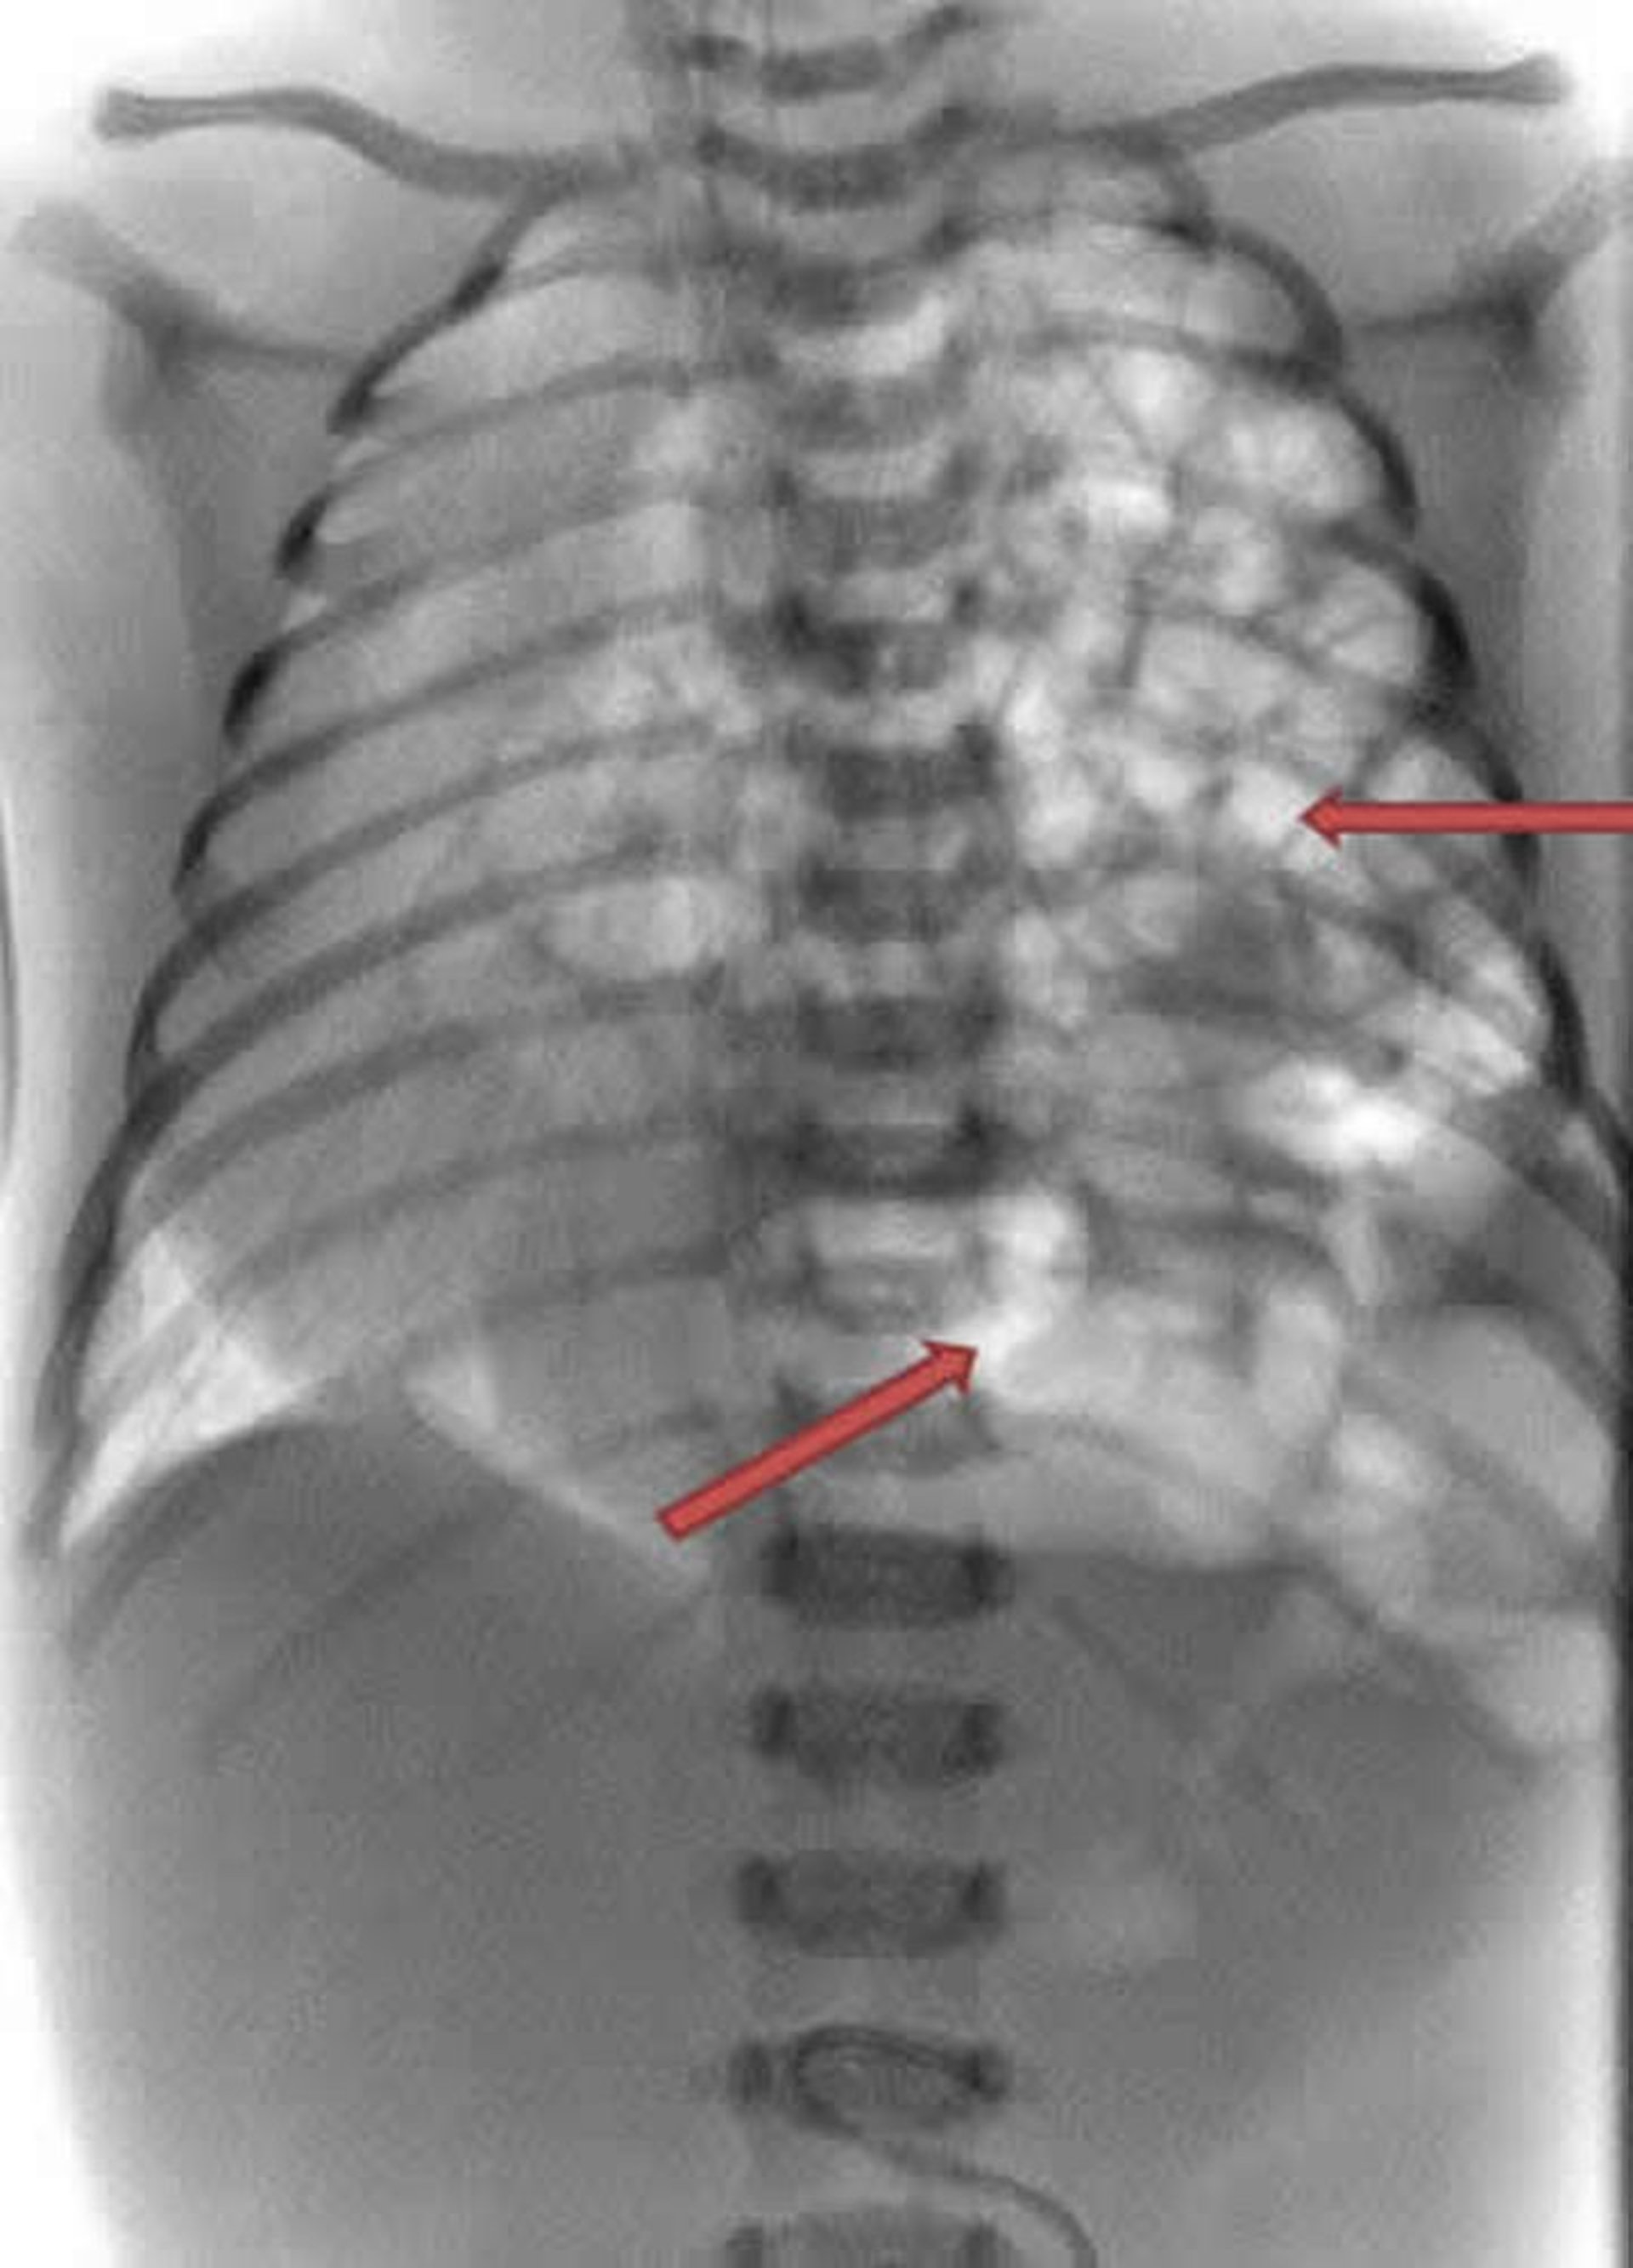

Questa radiografia di un neonato mostra la protrusione dell’intestino (spirale bianca) all’interno della parte sinistra del torace (frecce).